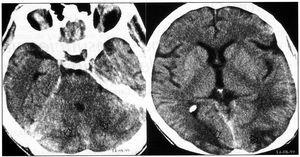

La biopsia renal (BR) demostró 18 glomérulos que presentaban afectación difusa de carácter isquémico con retracción y replegamiento de la pared capilar en las técnicas del PAS y argénticas, y rarefacción de la matriz mesangial. No se evidenció proliferación extracapilar. El intersticio presentaba fibroedema leve con infiltrado por células redondas, con atrofia tubular y cambios regenerativos del epitelio. Los vasos extraglomerulares de pequeño y mediano calibre presentaban cambios de arteriolopatía severa, necrosis fibrinoide de la pared y trombos fibrinoides intraluminales. La inmunofluorescencia fue negativa. Todo ello era compatible con HTA maligna (figura 2, figura 3 y figura 4).

Figura 2.